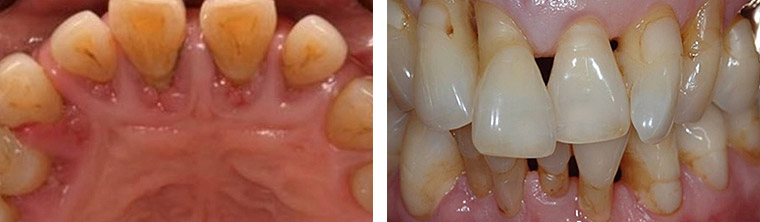

치주질환은 잇몸과 잇몸뼈 등 치아 주위 조직에 염증이 생겨

잇몸과 치조골을 파괴하는 질환으로 흔히 풍치라고 불리며 치은염과 치주염으로 나뉩니다.

치주염은?

치은염이 보다 진전된 상태로써 치조골과 인대까지 염증이 진행된 상태입니다.

치료하지 않고 놔둔다면 결국 치아가 흔들리게 되고 치아 발치를 해야하는 상황까지 됩니다.

치과에서 치료를 받으시는 것이 아주 중요하고 칫솔질시 잇몸에 피가 나고, 심한 입 냄새가 나고,

잇몸에서 고름이 나는 등의 증상을 보이며, 잇몸 사이에 공간이 생기며 치조골이 파괴되면서 치아가 흔들리게 됩니다.